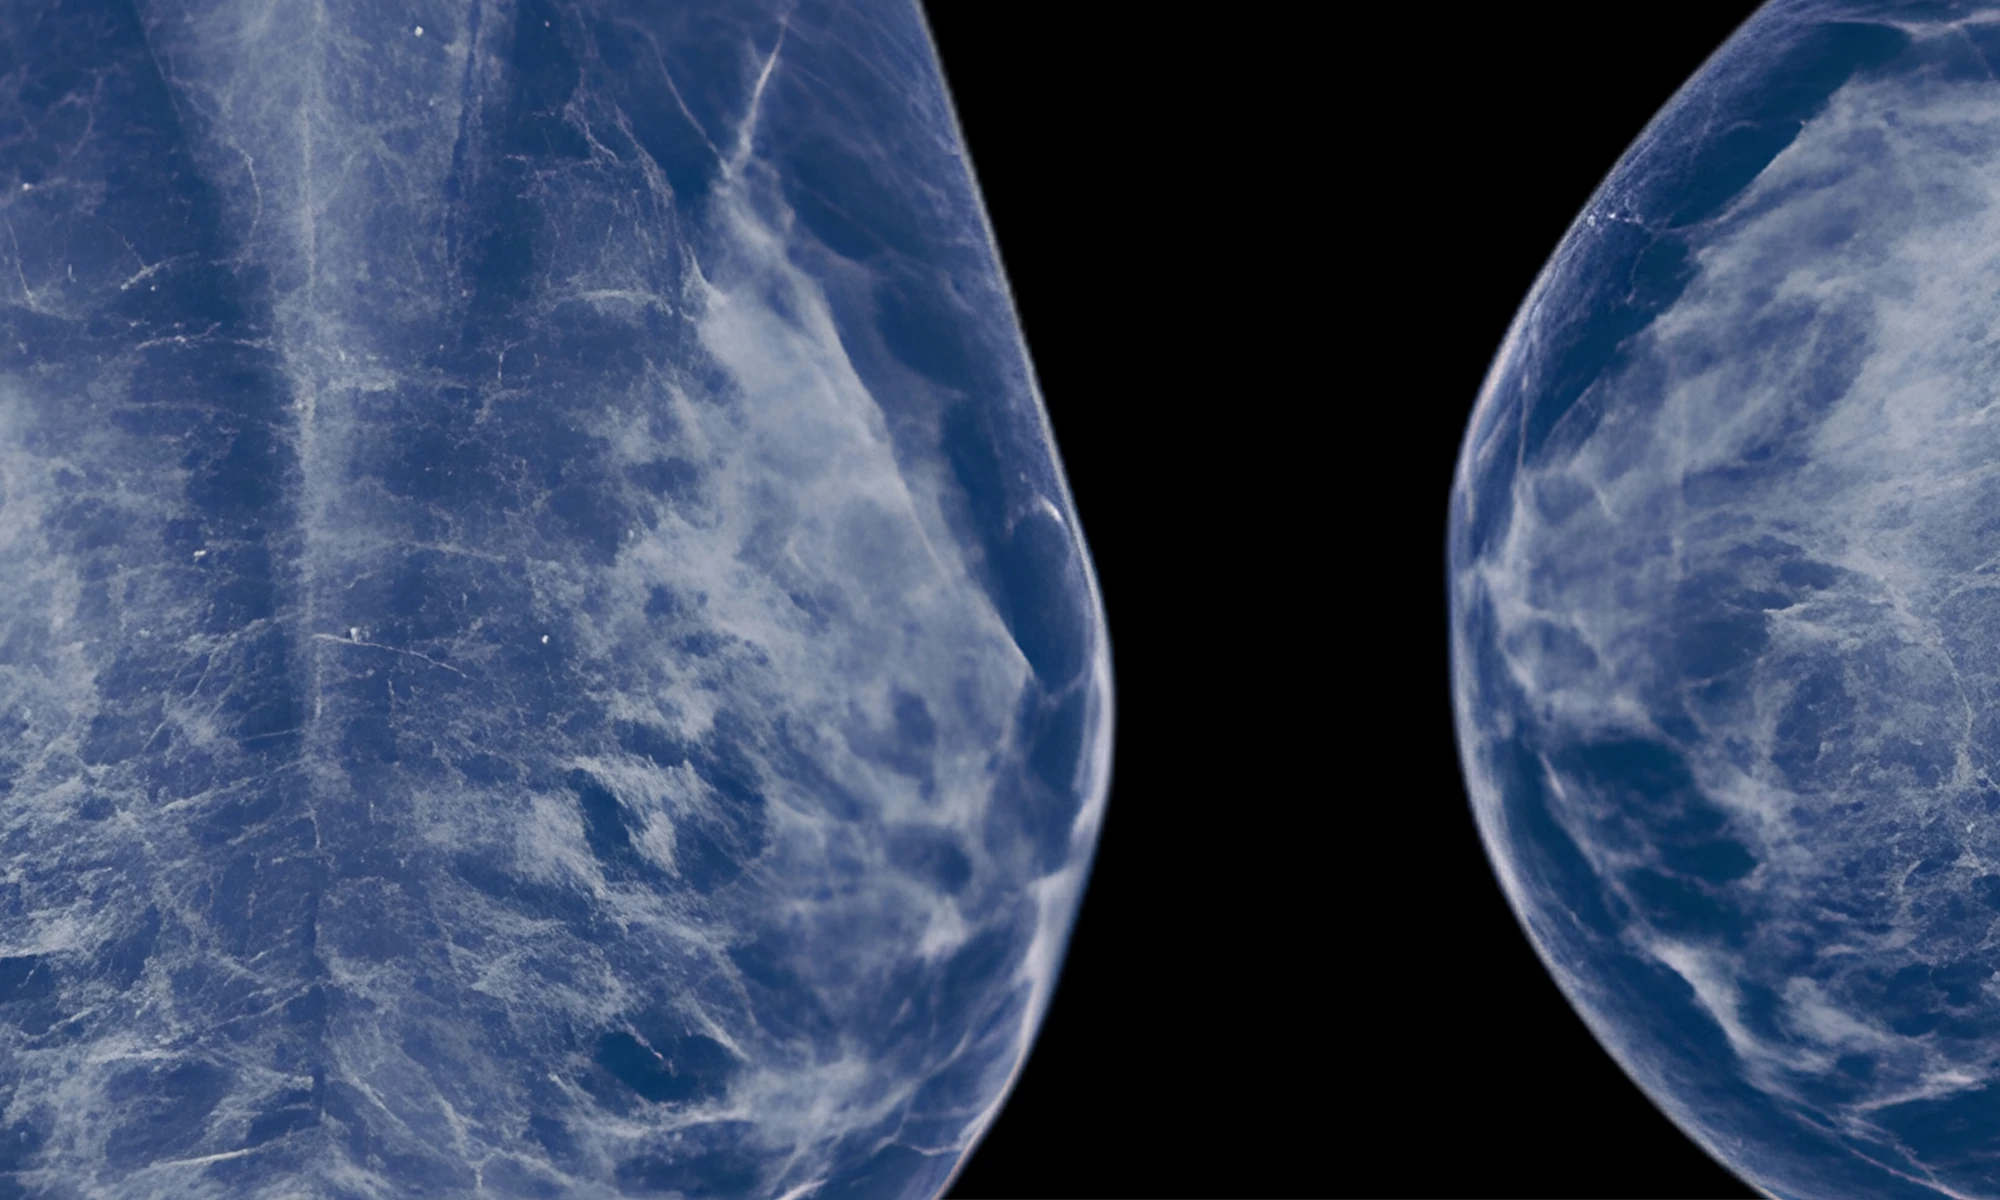

Predicting Cancer’s Path